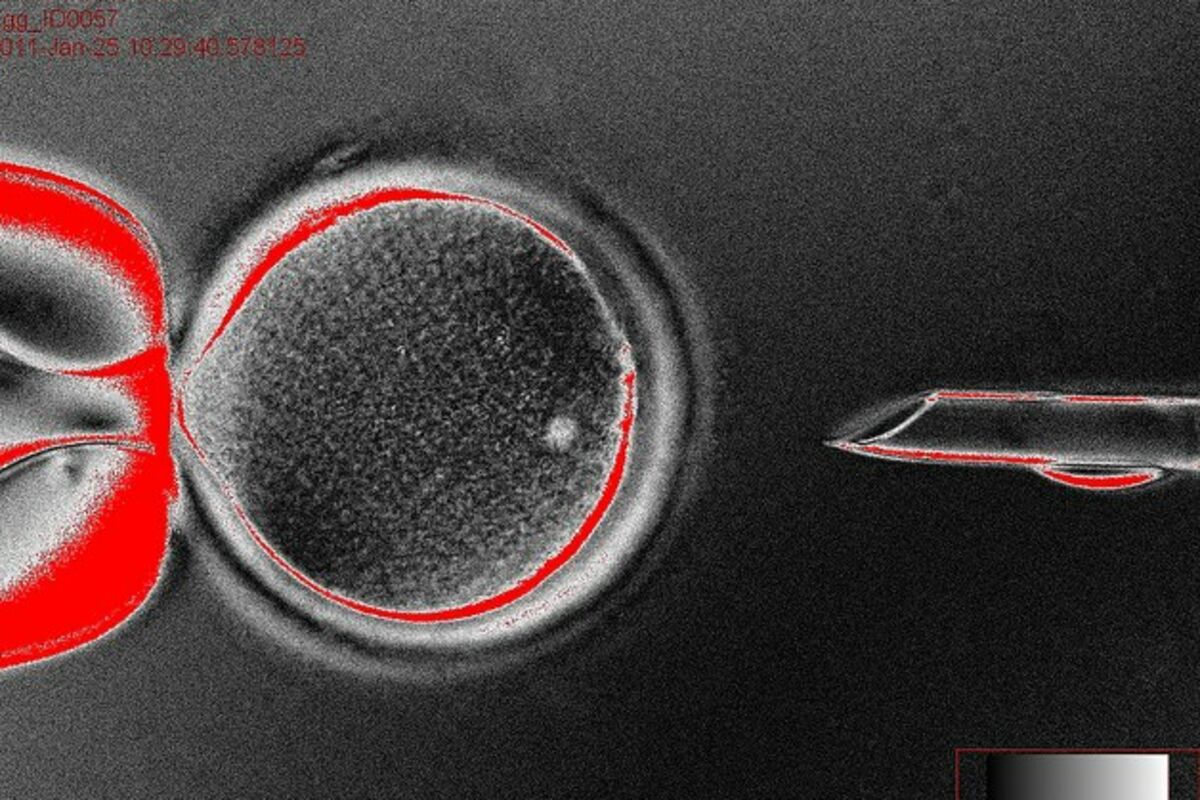

Matične ćelije, Foto: University of oregon